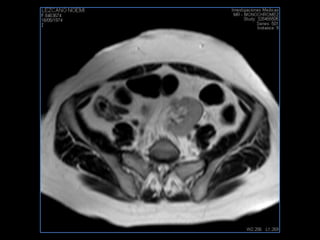

PROTOCOLO pelvis SAG T2, Y FAT SAT (FINOS) AXIAL T1  AX FAT SAT CON   GADOLINIO :  AX T1 Y COR T1 SAT: NO  FASE: RL THK: 3MM  COIL:  GAP: (FACTOR 1.4) 1MM FOV: 40 CM NEX:2 SINCRONIZACION RESPIRATORIA EN 3 O 4 CICLOS ALE

resonancia de abdomen